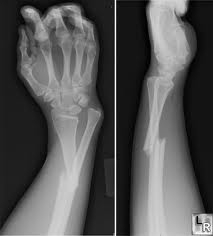

تعقد جمعية جراحة العظام المصرية، المؤتمر الدولى الثانى للإصابات والكسور، بالاشتراك مع قسم جراحة العظام بكلية الطب جامعة الإسكندرية، فى الفترة من 26 إلى 28 من الشهر الجارى بالإسكندرية. صرح الدكتور جمال أحمد حسنى، أستاذ جراحة العظام بكلية طب بنها ورئيس المؤتمر ورئيس جمعية جراحة العظام المصرية، بأن المؤتمر سيتناول الإصابات نتيجة الحوادث والكسور وأحدث الطرق فى علاجها، كما يتناول مضاعفات الكسور والحوادث والأساليب المبتكرة فى علاج هذه المشكلات. ويشارك فى المؤتمر حوالى 400 طبيب من مختلف الجامعات المصرية وجميع الدول الأجنبية والعربية، ويحاضر فى المؤتمر نخبة من الأطباء المصريين والأجانب. وأشار الدكتور حازم فاروق، استشارى جراحة العظام بطب قصر العينى وسكرتير عام المؤتمر، إلى أن القائمين على المؤتمر سيعقدون ورش عمل ودورات مكثفة لتدريب شباب جراحى العظام على أحدث الوسائل فى علاج الكسور فى التخصصات المختلفة فى جراحة العظام، مثل إصابات الملاعب والطب الرياضى وجراحات اليد والجراحات الميكروسكوبية وجراحات الحوض وأمراض عظام الأطفال، وأحدث ما توصل إلية العلم والتقنيات الحديثة فى مجال إصابات حوادث الطرق. وأكد أنه سيقوم بإلقاء المحاضرات نخبة من أساتذة الجامعات المصرية فى مختلف التخصصات وبعض الخبراء الأجانب.